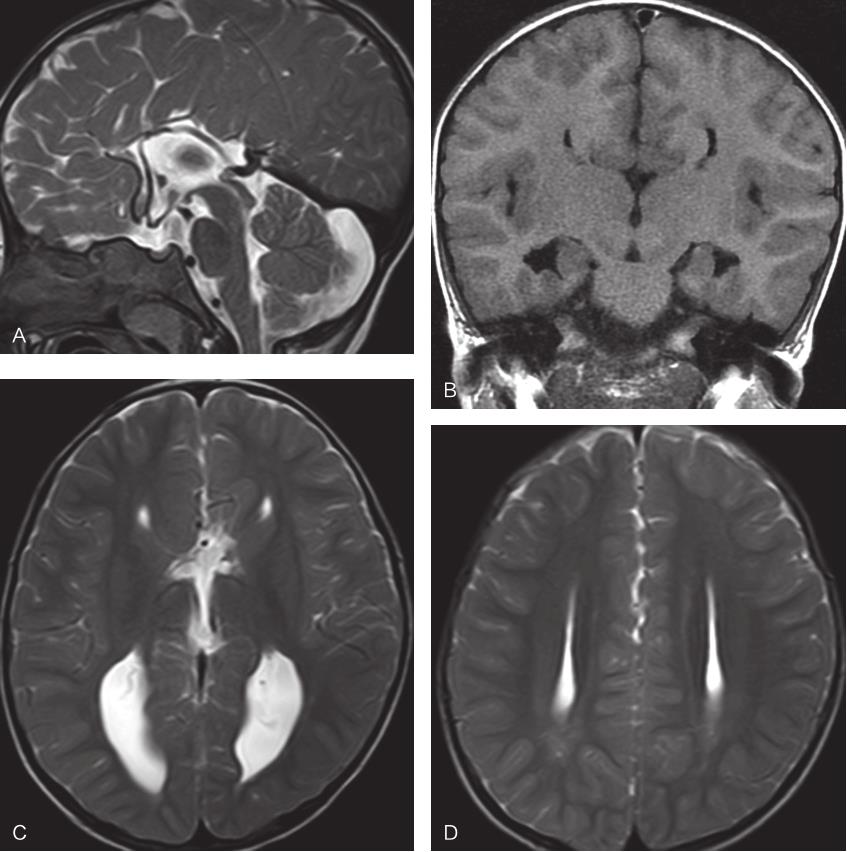

图2-3-4 胼胝体部分缺失MRI表现

A.矢状位T 2 WI示胼胝体喙部、压部及体后部缺失;B.横断位T 1 WI示胼胝体压部缺失

图2-3-5 胼胝体部分缺失伴灰质异位MRI表现

A.矢状位增强T 1 WI示胼胝体喙部缺如,体部形态不规则;B.冠状位T 1 WI示胼胝体体部形态不规则,左侧额叶灰质异位

图2-3-6 胼胝体膝部及喙部缺失伴Dandy-Walker畸形

矢状位T 2 WI示胼胝体膝部及喙部未见显示,小脑蚓部发育不全,第四脑室囊肿样扩张